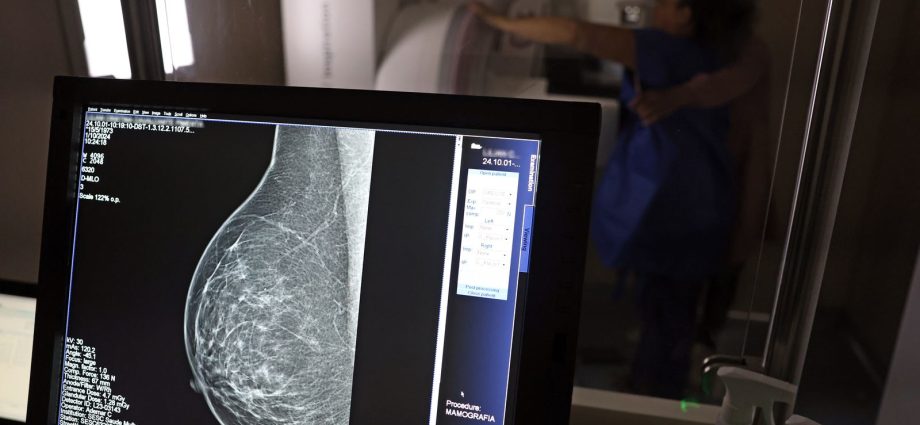

Com a nova lei, as empresas são agora obrigadas a informar os trabalhadores sobre seus direitos, incluindo a possibilidade de se afastar para a realização de exames preventivos. Além disso, as organizações também devem divulgar informações sobre campanhas de vacinação contra o HPV e sobre o acesso a serviços de diagnóstico para cânceres de mama, próstata e colo do útero.

Outra importante mudança trazida pela Lei 15.377 é a expansão do uso das folgas para incluir exames preventivos relacionados ao HPV. Essa adição é fundamental para promover uma abordagem mais abrangente à saúde do trabalhador, fortalecendo a prevenção de doenças que afetam significativamente a população.